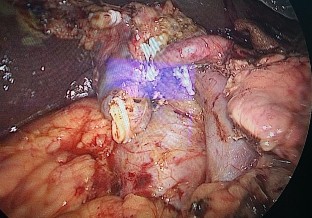

Bệnh nhân 2: Hoàng Quyết C, 1950 (69 tuổi) Mã số bệnh án: 18-03-20079

Chẩn đoán: Ung thư biểu mô bóng Vater

| |

Ảnh 1. Hình ảnh CLVT trước mổ | Ảnh 2. Sau cắt rời khối tá tụy |